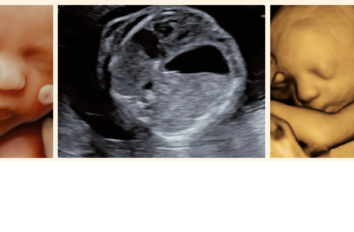

Mehrlingsschwangerschaften

Dr. med.  Ladina Vonzun,  Prof. Dr. med. Nicole Ochsenbein-Kölble

In den letzten 40 Jahren hat sich die Anzahl der Mehrlingsschwangerschaften in der Schweiz praktisch verdoppelt. Während 1979…